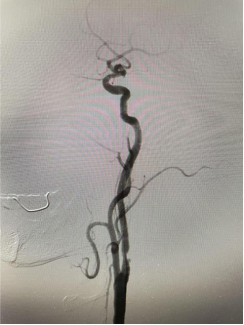

患者是一位古稀老人,已飽受高血壓病困擾,1月前行頭頸血管檢查可見雙側(cè)頸內(nèi)動脈狹窄80%以上,其發(fā)生中風(fēng)風(fēng)險極高?;颊呒覍僬业缴窠?jīng)內(nèi)科尋求進一步診治。因為患者高齡,雙側(cè)頸動脈嚴重狹窄,無頸動脈內(nèi)膜剝脫術(shù)(CEA)指征,科室團隊討論后決定為其行頸動脈支架植入術(shù)(CAS)。對于介入治療,該患者也面臨同期或分期完成雙側(cè)頸動脈支架植入治療的選擇。分期雙側(cè)頸動脈支架植入有增加病人痛苦、住院時間長和費用增加的缺點,以及術(shù)中、術(shù)后低灌注引起未治療側(cè)腦梗死,術(shù)后高灌注造成治療側(cè)腦出血等風(fēng)險。同期雙側(cè)頸動脈支架植入術(shù)增加手術(shù)操作的時間和難度,雙側(cè)頸動脈狹窄同時解除會使顱內(nèi)血流迅速增加,與分期手術(shù)相比,可能會增加潛在的高灌注綜合征發(fā)生的風(fēng)險,同時刺激雙側(cè)頸動脈竇壓力感受器,可能會導(dǎo)致更嚴重、持久的血流動力抑制,甚至心跳驟停。通過與家屬積極溝通,科室團隊充分討論后,決定采用同期雙側(cè)頸內(nèi)動脈支架植入術(shù)治療方案??剖覉F隊完善術(shù)前準備,制定各項手術(shù)應(yīng)急預(yù)案和措施,手術(shù)順利。術(shù)后科室團隊密切監(jiān)護患者生命體征,無神經(jīng)功能缺損癥狀出現(xiàn),現(xiàn)患者痊愈出院。

(右側(cè)頸內(nèi)動脈治療前) (左側(cè)頸內(nèi)動脈治療前)